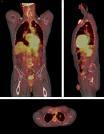

January 13, 2010 - Compared to computed tomography (CT), mammography and other commonly used tests, positron emission tomography-computed tomography (PET/CT) scans of the whole body may more accurately detect cancer in individuals with related neurologic disorders, according to a report posted online today that will appear in the March print issue of Archives of Neurology, one of the JAMA/Archives journals. Andrew McKeon, M.B., MRCPI, and colleagues at Mayo Clinic, Rochester, Minn., found paraneoplastic neurologic disorders occur in some people with cancer, including lung, breast or ovarian cancer, and may develop when cancer-fighting antibodies mistakenly attack cells in the nervous system. The researchers found that "patients with suspected paraneoplastic neurologic disorders, routine noninvasive oncologic evaluations may be unrevealing." The authors noted, "These standard evaluations include physical examination; computed tomography (CT) of the chest, abdomen and pelvis; mammography in women; and testicular ultrasonography and prostate-specific antigen testing in men." Cancers underlying paraneoplastic neurologic disorders are typically small, restricted to one site and are often not detected until autopsy. The researchers studied cases of 56 patients with suspected paraneoplastic neurologic disorders whose standard evaluations (including CT) did not reveal cancer. All of them underwent PET-CT at Mayo Clinic between 2005 and 2008. Prior to undergoing PET/CT exams, the patients underwent a median of three other screening tests; the most common was CT of the chest, abdomen and pelvis. In 39 percent of the patients, PET/CT detected abnormalities suggestive of cancer, of whom 18 percent had cancer diagnoses confirmed by biopsy or another method. Nine of the 10 were early-stage cancers, and detection facilitated early treatment. Cancer remission was reported in seven patients and improvement in neurologic symptoms in five patients after a median (midpoint) of 11 months of follow-up. While the authors noted they recognize the limitations of PET/CT, they said, "We favor this modality for initial oncologic evaluation of patients in whom a paraneoplastic neurologic disorder is strongly suspected. Elimination of whole-body imaging with CT alone before further imaging with PET/CT could reduce radiation exposure and the total financial burden of testing." Reference: Arch Neurol. 2010;67(3)]: doi:10.1001/archneurol.2009.336. For more information: jama-archives.org and http://archneur.ama-assn.org